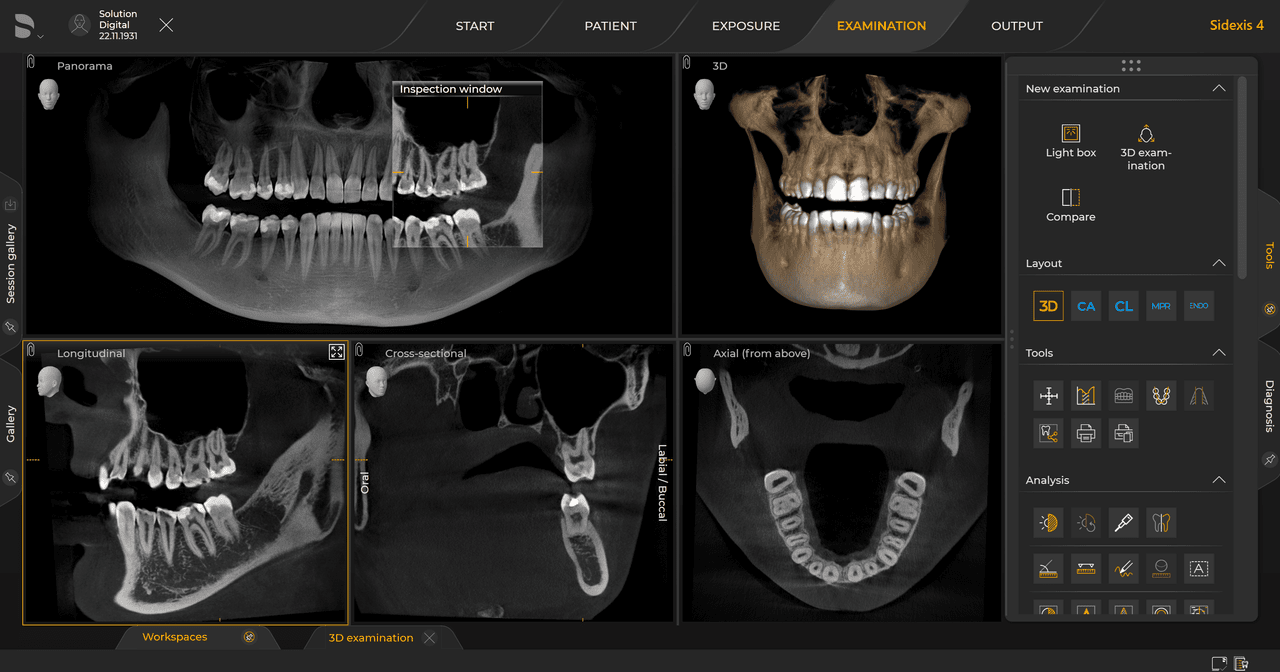

Los requisitos siguen los del software de procesamiento de imágenes Sidexis 4 y Orthophos S. Para obtener más detalles, consulte los requisitos del sistema Sidexis 4 y los requisitos de instalación de Orthophos S.

Las unidades de radiología de Dentsply Sirona funcionan exclusivamente con Sidexis 4. Sin embargo, la migración de datos de Sidexis XG a Sidexis 4 es muy fácil. Sidexis 4 permite una experiencia digital completa con las últimas herramientas

Orthophos S de 2D permite una actualización 3D. Axeos es una unidad híbrida exclusiva. El Orthophos E no ofrece esta opción.